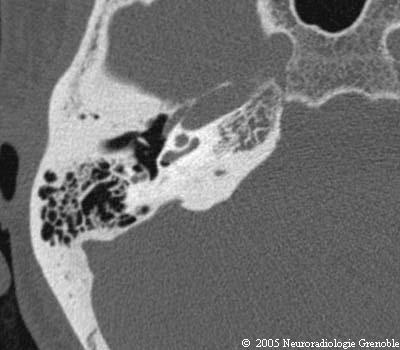

Radioanatomie TDM du rocher normal

Cochlée (tour basal)

Cochlée (2ème tour)

Fenêtre cochléaire (ronde)

Aqueduc de la cochlée

Aqueduc du vestibule

Marteau (manche)

Enclume (processus lenticulaire)

Membrane tympanique

Canal du muscle de l'étrier et pyramide

Canal du facial (3ème portion)

Canal du muscle du marteau

Cellule épitympanique antérieure

Mésotympan

Sinus tympani

Cellules mastoïdiennes

Méat acoustique externe